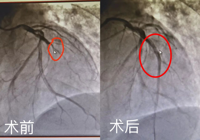

- 急性心肌梗死(sǐ)是由於心髒的動脈血管突然閉塞導致心肌急性缺血缺(quē)氧而(ér)發(fā)生壞(huài)死,是內科的急危重症,死亡率可達30-50%。近日,武寧縣人民醫院成功(gōng)救治一位急性心...2023-08-25